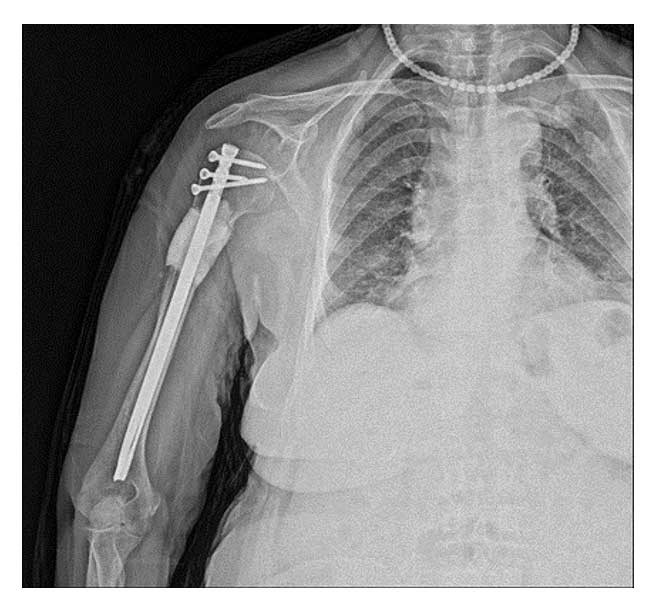

Ameliyat Sonrası: Röntgende kemiğin tümörlü kısmının tek parça halinde temiz sınırlar ile çıkarılması sonrası oluşan boşluğun kemik çimentosu ile doldurulması ve kapalı titanyum çivi ile güçlendirilmesi işlemi görülmekte.